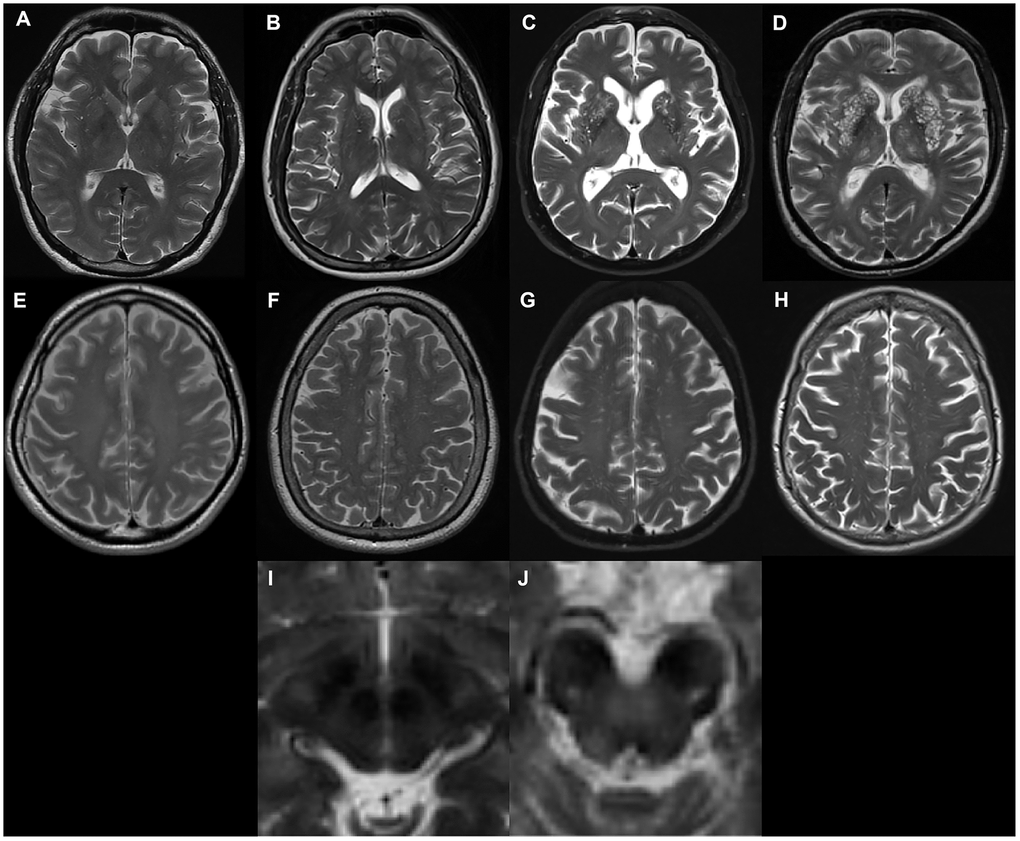

EPVS were defined as fluid-filled spaces with a signal intensity similar to CSF on all sequences, which followed the course of penetrating vessels, and were linear, round, or ovoid in shape. Following the STandards for ReportIng Vascular changes on nEuroimaging (STRIVE) [1], two trained neurologists (L.Y.G. and J.T. with 2-years and 9-years of experience, respectively), who were blinded to subject’s clinical information, manually counted the numbers of EPVS independently. According to well-established PVS rating criteria [43], EPVS were rated using a 4-point visual rating scale on axial-T2 weighted images (0: no EPVS; 1: <10 EPVS; 2: 11–20 EPVS; 3: 21–40 EPVS; and 4: >40 EPVS) for the CSO and BG. Midbrain EPVS were rated in a binary fashion (0 for no EPVS, 1 for EPVS visible). EPVS rating was carried out on the slice with the highest number of EPVS after all the relevant slices for each anatomic area were scanned. Both hemispheres were counted, and the hemisphere with the higher score was used if there was asymmetry between the sides [43]. 'Representative figures of EPVS rating are demonstrated in Figure 3. As a limited number of patients had EPVS scores of 0 or 4, CSO-EPVS scores were further categorized into low-grade (score ≤ 2) and high-grade (score ≥ 3) and BG-EPVS scores were categorized into low-grade (score ≤ 1) and high-grade (score ≥ 2) for illustrative purposes. These categorizations are demonstrated in the figures; however, statistical analysis was carried out using the original values. Discrepancies were solved by consensus. T2-weighted images acquired at baseline were preferentially rated. In a few cases when images were not acquired at baseline, images acquired at follow-up visits were rated. The inter-rater Cohen’s kappa scores were 0.63, 0.75, and 0.96 for the CSO, the BG and the midbrain EPVS scores, respectively. Major causes of discrepancies in EPVS scores included EPVS numbers at borderline, and vague lines.

Figure 3. Examples of MRI-visible perivascular spaces. (A–D) Examples of MRI-visible BG-EPVS. (A) grade 1; (B) grade 2; (C) grade 3; (D) grade 4. (E–H) Examples of MRI-visible CSO-EPVS. (E) grade 1; (F) grade 2; (G) grade 3; (H) grade 4. (I) Example of no MRI-visible midbrain-EPVS. (J) Examples of MRI-visible midbrain-EPVS.